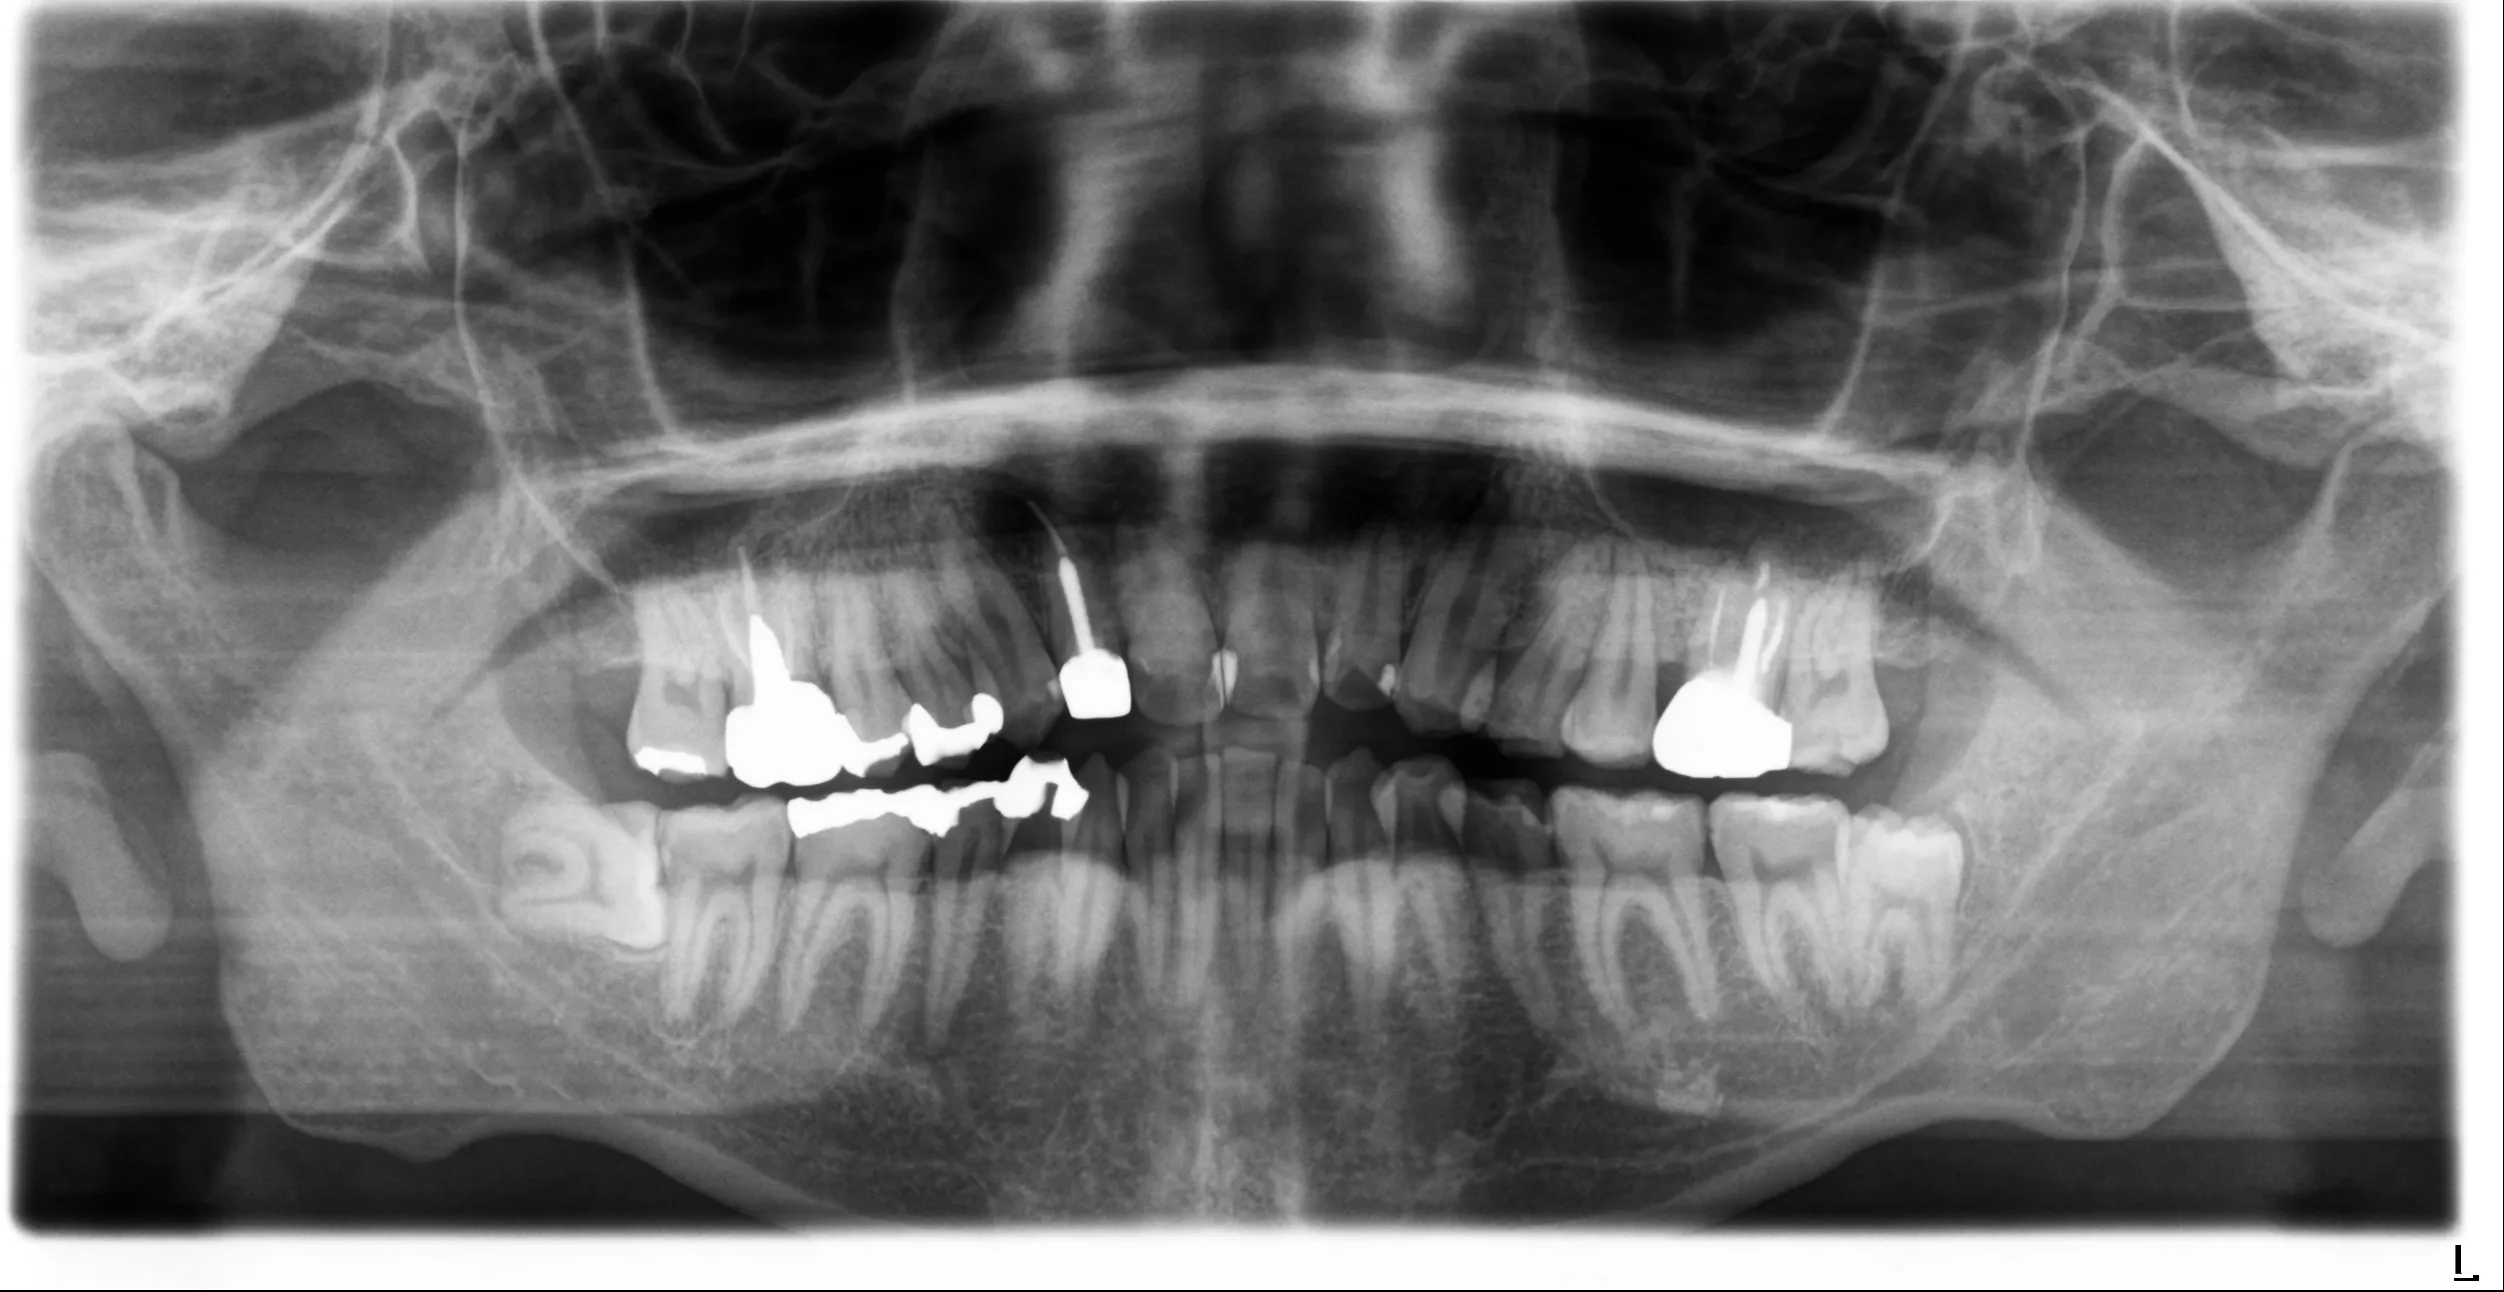

before

after

CASE 01

精密根管治療